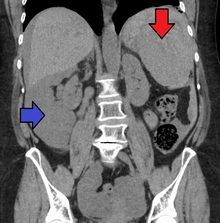

Splenic rupture is usually evaluated by FAST ultrasound of the abdomen.[3] Generally this is not specific to splenic injury; however, it is useful to determine the presence of free floating blood in the peritoneum.[3] A diagnostic peritoneal lavage, while not ideal, may be used to evaluate the presence of internal bleeding a person who is hemodynamically unstable.[4] The FAST exam typically serves to evaluate the need to perform a CT.[4] Computed tomography with IV contrast is the preferred imaging study as it can provide high quality images of the full peritoneal cavity.[3]